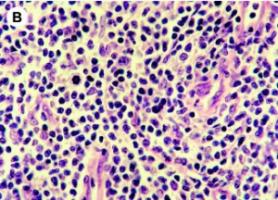

LYMPHOME associé au virus d'Epstein-Barr: Une nouvelle immunothérapie adoptive